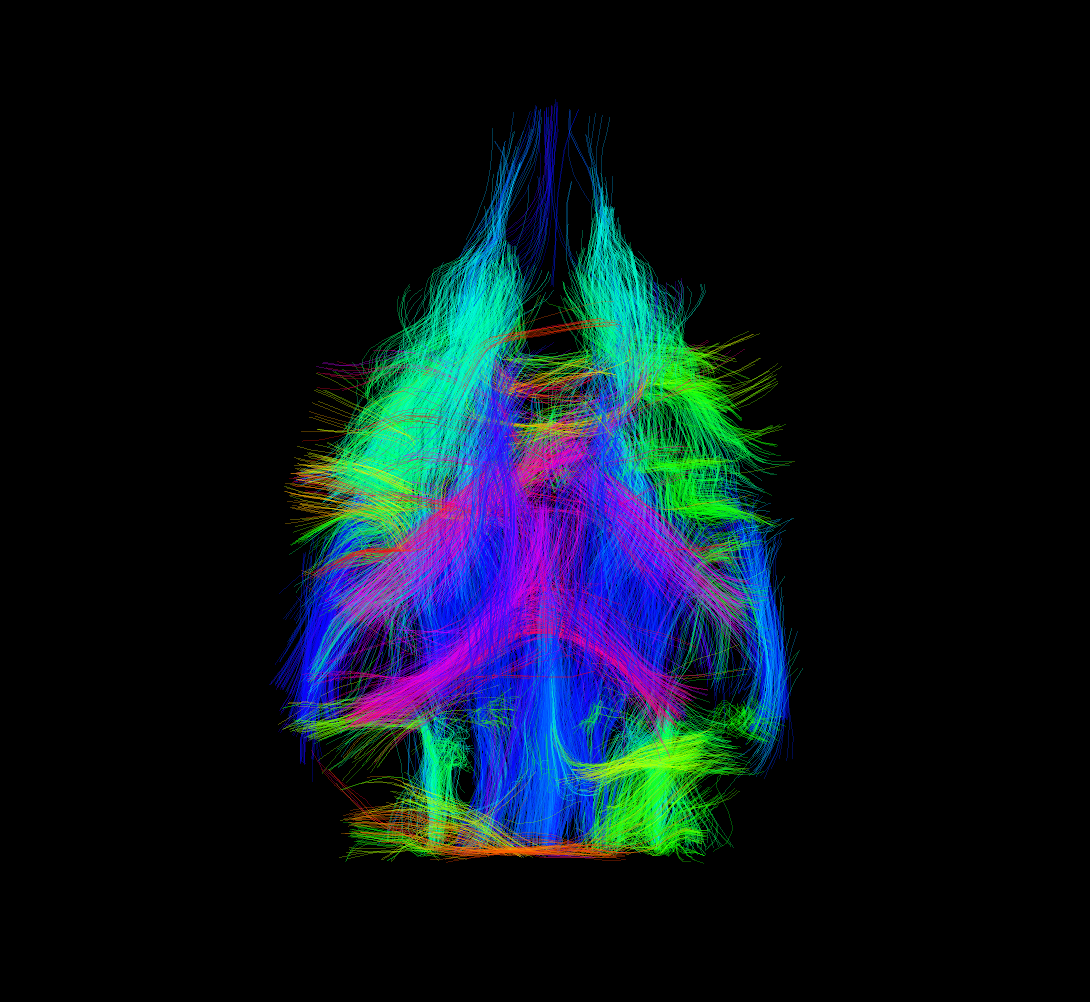

- Difüzyon tensör görüntüleme (DTI), traktografi

Difüzyon Görüntüleme Uygulamaları

Dokulardaki (örneğin beyin, karaciğer) difüzyon özellikleri difüzyon ağırlıklı görüntüleme sekansları ile değerlendirilebilmektedir. Buna ek olarak, beyindeki beyaz cevher yolaklarının fraksiyonel anizotropi (FA) gibi ayrıntılı özelliklerini değerlendirmeye ve traktografisine olanak tanıyan difüzyon tensor görüntüleme yapılabilmektedir.